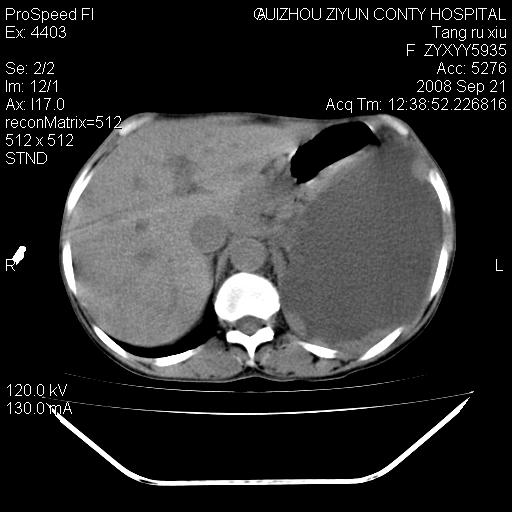

肝脏大小形态尚可,其实质内可见多发大小不等的低密度影,边缘模糊。肝门区结构紊乱,腔静脉腹主动脉旁可见多发软组织密度影,部分融合成团块状,并向下延伸。胰腺及十二指肠结构显示不清。腹腔内脐后肠管走形僵硬,管壁可见增厚。盆腔内可见多个淋巴结影。所扫层面左侧胸腔可见大量弧形水样密度影,其内侧可见被压缩的肺组织影。左侧胸壁可见一小结节样软组织密度影,边缘模糊。心脏纵隔向右侧移位。心脏包膜内可见囊样低密度影,其内侧心房室周围可见一圈气体样密度影。纵隔内大血管旁可见多发软组织团块影,部分融合。

1.腹膜后淋巴瘤侵及肝脏,肺内及纵隔内多发转移。2.左侧大量胸腔积液并压缩性肺不张。3.心包脓肿可能,转移不除外。4.脐后局部肠管管壁增厚,考虑炎症可能,肿瘤不除外。

左侧中心型肺癌并胸膜及心包转移。肝内转移,腹膜后淋巴结转移。

考虑左侧肺癌侵犯纵隔,左侧胸膜、肝脏及腹膜后淋巴结转移。心包积液及左侧胸腔积液。